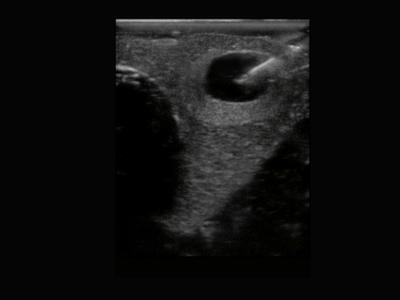

Tiroid içerisinde saptanan ve tümöral gelişim açısından riskli olduğu düşünülen noduler lezyonlarda tirod iğne biyopsisi yapılmalıdır.Bu işlem poliklinik koşullarında, lokal anestezi altında yapılır. Ultrason eşliğinde ince bir iğne ile biyopsi yapılacak kitle ya da nodul içerisine girilerek vakum yöntemi ile örnek alınmaya çalışılır.Bu işlem birkaç kez tekrarlanabilir. Birden fazla şüpheli nodul olması durumunda her birinden ayrı ayrı biyopsi yapılır.

Alınan örnekler lam adını verdiğimiz cam plakalara yayılarak patoloji labaratuvarına gönderilir. Çıkan patolojik sonuca göre tedavi planlanır.Tiroid iğne biyopsisi minimal ağrılı bir işlem olup sonrasında hastanede yatış gerektirmez. Hasta biyopsi sonrasında günlük işlerine devam edebilir.